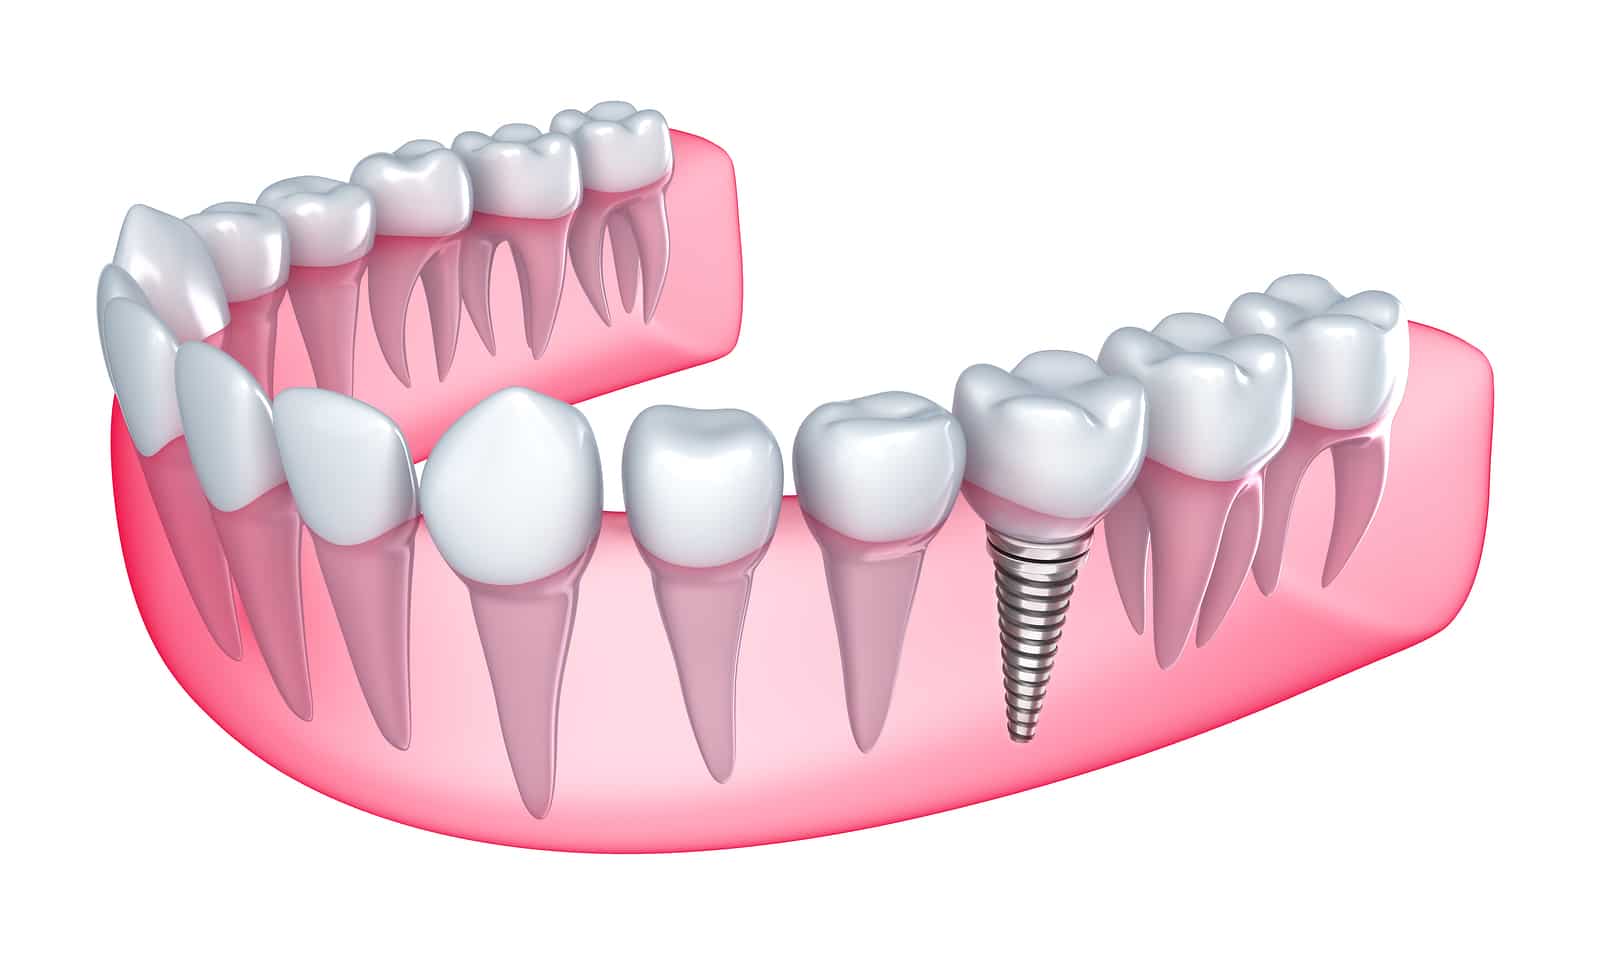

A dental implant is a small titanium post surgically placed into the jawbone to act as an artificial tooth root. Once integrated with the bone, it provides a solid foundation for a crown, bridge, or denture. The stability offered by dental implants mimics natural teeth, making eating and speaking significantly easier compared to other options.

- Surgical Placement: The implant post is carefully inserted into the jawbone. Over time, the bone fuses with the implant through a process called osseointegration, creating a durable foundation.

- Crown Placement: After successful integration, a custom-made crown is attached to the implant. This final step restores the tooth’s appearance and functionality.